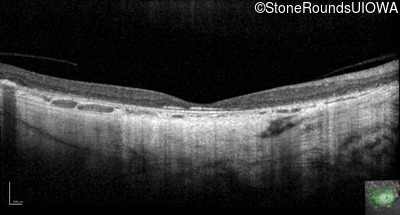

Optical Coherence Tomography - Left - 10/200

Exemplar / OCT Stack